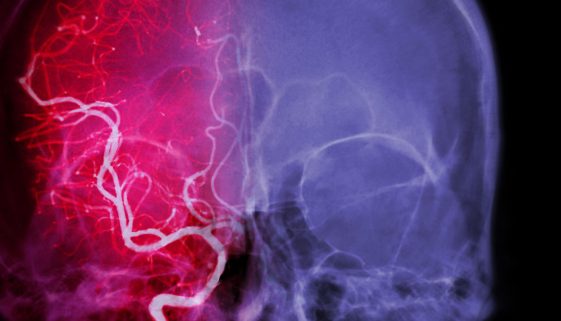

نصائح وتعليمات تثقيفية بخصوص علاج حالات نزيف المخ

يُعتبر نزيف المخ من الحالات الطبية الطارئة التي تتطلب رعاية فورية وعناية مركزة. يُعرف أيضًا بالنزيف الدماغي، ويحدث عند تمزق أوعية دموية داخل المخ، مما يؤدي إلى تجمع الدم. هذا التجمع يزيد من الضغط على أنسجة المخ، ويؤدي إلى تلف الخلايا. في هذه المقالة، سنستعرض النصائح والتعليمات التثقيفية بخصوص علاج […]